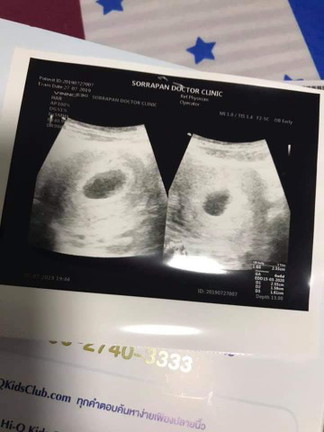

ซาวด์เจอน้องกี่ week ค่ะ เรา 6week6day ยังไม่เจอเลยค่ะ

หมอบอกยังไม่เจอการเต้นของหัวใจน้องคะ เดือนกว่าแล้ว อาจจะท้องลม หรือไม่ก็น้องตัวเล็กจนซาวด์ไม่เห็น

ใจเย็นๆนะคะคุณแม่ ไข่อาจจะตกช้าค่ะ รออีกสัก2อาทิตย์นะคะ บ้านนี้ก็ประมาณ8weekค่ะที่เจอตัวน้องและหัวใจ